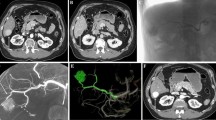

Selective internal radiation therapy (SIRT) is a relatively new, catheter-directed treatment modality of both primary [45] and secondary [46, 47] liver tumors. In contrast to transarterial chemoembolization (TACE), an angiographic work-up is required prior to yttrium-90 (Y-90) loaded microsphere infusion into the hepatic artery [48]. Angiographic work-up mainly consists in identifying (and, if indicated, coil-embolizing) hepatoenteric arteries, originating from the hepatic arteries [49]; defining the vascular territory of all targeted hepatic arteries; and identifying the tumoral lesions within these vascular territories. Additionally, total volume calculation of the hepatic vascular territory and targeted liver tumors is important to correctly calculate the total dose of yttrium-90 microspheres to be injected in the targeted hepatic arteries (Fig. 5), as well as fraction shunted to lung.

a–e Diffuse metastatic tumoral involvement of both liver lobes in a 67-year-old woman presenting with chemorefractory liver metastases from breast carcinoma. Angiographic work-up prior to Y90-radioembolization included CBCT imaging demonstrating the vascular territory of right and left liver lobe. The vascular territory of both hepatic arteries does not fully agree with the morphological division into the right and left liver lobe

Digital subtraction angiography (DSA) is the gold standard to identify hepatoenteric arteries. However, Louie et al. [50] demonstrated that CBCT identified extrahepatic contrast enhancement in 52 % of cases. In 33 % of cases these additional CBCT observations, not demonstrated by DSA, lead to additional coil embolization and/or change in catheter position. Finally, in 19 % of cases, extrahepatic enhancement was, even in retrospect, not detected by Tc99-MAA imaging.

Total liver, lobar, and tumor volume measurements are typically performed based on conventional CT or MRI. However, parts of tumoral mass lesions located in the right or left liver lobe might be vascularized by the contralateral hepatic artery, which, potentially, might lead to miscalculation of the liver and tumor volume and finally might result in over- or undertreatment of one or both liver lobes resulting in suboptimal clinical outcome (Fig. 6). CBCT depicts perfused tissue location, which is essential for correct segment classification or pre-treatment portal vein embolization.

a–d CBCT imaging during Y90 work-up in a 60-year-old patient suffering from chemorefractory colorectal liver metastases clearly shows a small hepatoenteric vessel, feeding the gastric wall: right gastric artery. Using Emboguide, the small hepatoenteric vessel was identified on angiography. Subsequently, proximal coil embolization of the right gastric artery was performed